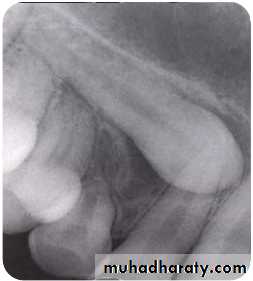

Tube shift technique or Clarke

technique (parallax method)

Principle:

• 2 periapical views of the same object are taken from slightlydifferent angles which can provide depth to the flat 2-D

picture depicted by each of the films individually.• Useful in distinguishing the buccal or lingual displacement of

Mesialangulation

Normal

angulation

Distal

Procedure:

1.In the periapical film, the X-rayis taken in the area of interest

with the X-ray beam passing

perpendicular to a tangent to

the line of arch at this point & at

an appropriate angle to

horizontal plane.

2.In the second film, the X-ray

tube is shifted mesially ordistally round the arch but held

at the same angle to the

horizontal plane. The X-ray

tube should describe between

30-450 of an arc of circle whose

Result:

• It is based on the SLOB principle.

• If the object has moved on the same side as thatof the X-ray tube it is lingually placed & if it has

moved on the opposite side it is on the buccalside.

Disadvantage:In cases when canine is highly placed, and

Periapical film shows no superimposition of canine

with the roots of erupted tooth or when

Vertical tube shift method

Left canine is highly placed in OPG. In IOPA left canine moves towards apical 1/3 of lateral

incisor.73